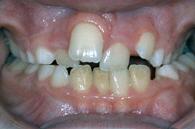

Hier ist eine Behandlung angesagt